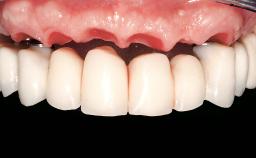

Immediate Loading of Eight Implants in the Maxilla and Six Implants in the Mandible and Final Restoration with Three-Unit and Four-Unit FDPs